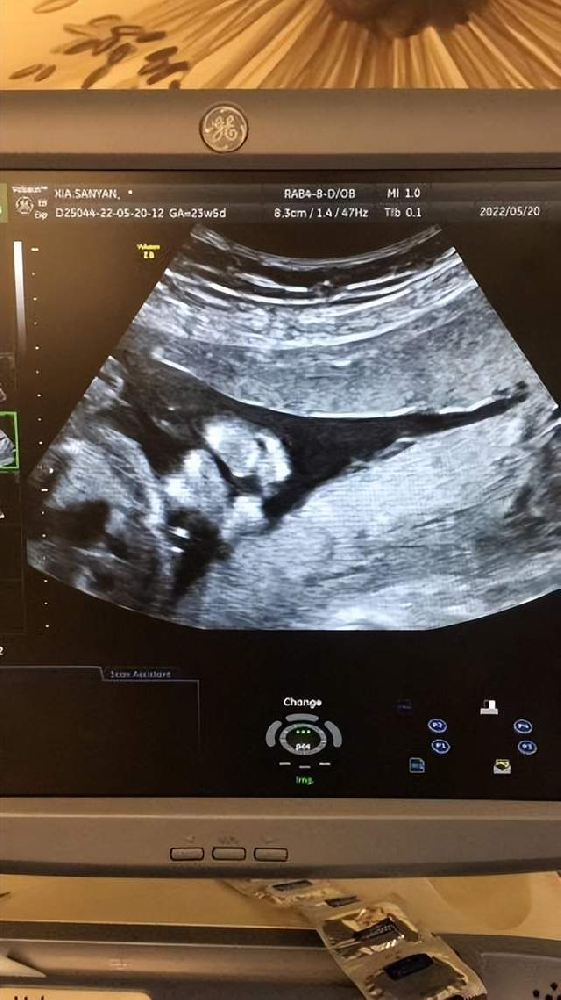

新生命的誕生對于一個(gè)家庭來說是再幸福不過的一件事。隨著生育政策的放開,越來越多的家庭選擇生育二胎。但在迎接新生命的同時(shí),許多“二胎”孕婦認(rèn)為自己已經(jīng)是“熟手”,···